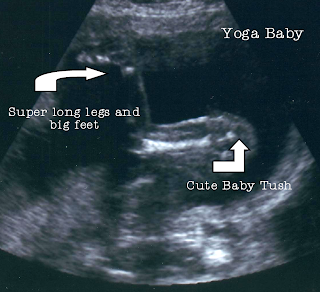

Just a little preview of Bun in Oven. It was a long ultrasound, for many reasons, and I need to go in next week for an even more in-depth ultrasound due to a possible complication (vague enough for you?) So far, except for that one little (possible) blip, everything looks good - and pretty darn cute, if I do say so myself. Say a little prayer that I don't freak out too much before I get to the perinatologists next week -- because we all know the levels of freak-out of which I am capable!

ReplyDeleteVery cute pictures! I love those long legs that baby obviously got from Rob.

ReplyDeleteaaaawww! i think it's just amazing how they suck their thumbs in the womb.

Love the pictures. The sucking the thumb ones are always the best. We will say a prayer or two for you. :)